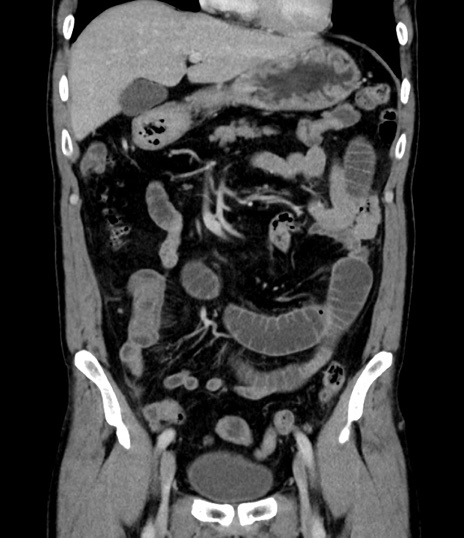

症例8(冠状断像)

【症例】 60歳代男性

【主訴】 黒色吐物

【現病歴】 4日前から嘔気自覚、2日前の朝食後にも嘔気あり、自分で手で嘔吐反射起こし嘔吐したところ血が混ざっていたため受診。

【既往歴】 5年前汎発性腹膜炎を伴う急性虫垂炎で手術、高血圧、前立腺肥大症、高脂血症

【身体所見】 腹部正中に手術癩痕あり 腹部平坦・軟圧痛なし膨満感あり

【データ】WBC 8400、CRP 4.54